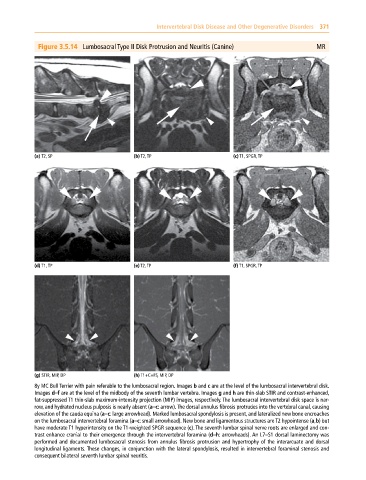

Figure 3.5.14 Lumbosacral Type II Disk Protrusion and Neuritis (Canine) MR

(a) T2, SP (b) T2, TP (c) T1, SPGR, TP

(d) T1, TP (e) T2, TP (f) T1, SPGR, TP

(g) STIR, MIP, DP (h) T1+C+FS, MIP, DP

8y MC Bull Terrier with pain referable to the lumbosacral region. Images b and c are at the level of the lumbosacral intervertebral disk.

Images d–f are at the level of the midbody of the seventh lumbar vertebra. Images g and h are thin‐slab STIR and contrast‐enhanced,

fat‐suppressed T1 thin‐slab maximum‐intensity projection (MIP) images, respectively. The lumbosacral intervertebral disk space is nar

row, and hydrated nucleus pulposis is nearly absent (a–c: arrow). The dorsal annulus fibrosis protrudes into the vertebral canal, causing

elevation of the cauda equina (a–c: large arrowhead). Marked lumbosacral spondylosis is present, and lateralized new bone encroaches

on the lumbosacral intervertebral foramina (a–c: small arrowhead). New bone and ligamentous structures are T2 hypointense (a,b) but

have moderate T1 hyperintensity on the T1‐weighted SPGR sequence (c). The seventh lumbar spinal nerve roots are enlarged and con

trast enhance cranial to their emergence through the intervertebral foramina (d–h: arrowheads). An L7–S1 dorsal laminectomy was

performed and documented lumbosacral stenosis from annulus fibrosis protrusion and hypertrophy of the interarcuate and dorsal

longitudinal ligaments. These changes, in conjunction with the lateral spondylosis, resulted in intervertebral foraminal stenosis and

consequent bilateral seventh lumbar spinal neuritis.